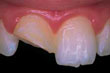

Diente astillado después de la reparación

Dientes astillados: si no siente dolor y la astilla es pequeña, usted deberá decidir si se hará reparar ese diente, cómo y cuándo. Según el tamaño de la astilla, el dentista lo alisará o corregirá cosméticamente. Otras opciones incluyen revestimientos, coronas y restauraciones. Si una restauración o un diente artificial se astilla, hay que reemplazarlo.